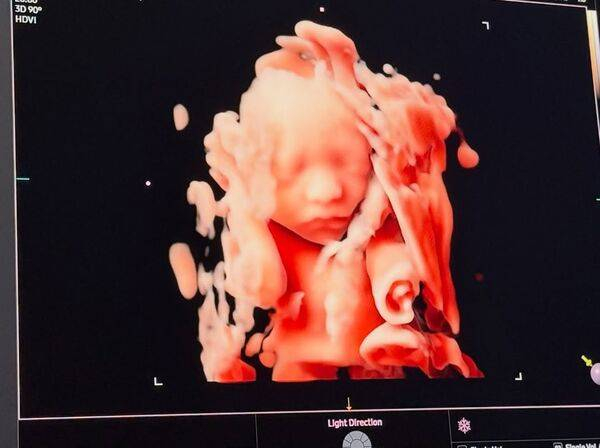

前FTISLAND成员宋承炫近年淡出演艺圈后,人生迎来全新阶段。21日他在社群平台分享了两张超音波照片,并写下“就快见面了,我们的小太阳”,疑似公开即将升格当爸爸的喜讯,消息一出立刻引发关注。

宋承炫在2024年与圈外女友结婚并移居美国生活。从他曝光的照片中可以看到,一张为黑白超音波影像,另一张则为3D立体超音波,能清楚看到宝宝的脸部轮廓与姿态,画面温馨又充满期待,也让粉丝纷纷留言祝福。